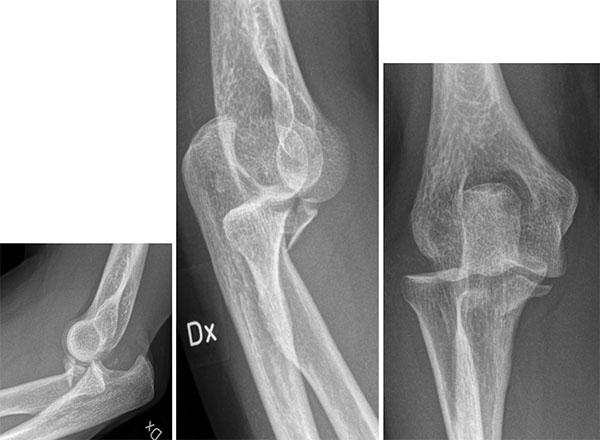

Resultat: De nya ytersättningsproteserna introducerades av främst McMinn och Amstutz strax efter sekelskiftet 2000 och fick ett betydande genomslag, inte minst som protes för unga och aktiva ”idrottsprotes” (bild till höger). Rapporter om komplikationer med höga nivåer av metalljoner, destruerande

mjukvävnad runt leden (pseudotumör) och collumfrakturer började dock relativt snart påverka entusiasmen.

En av tillverkarna drog 2010 in sin protes med omedelbar verkan. Men nästan 100 000 patienter hade då redan blivit opererade med denna protes. Härefter har metoden snabbt minskat i användning – även om vissa ”entusiaster” fortsätter att genomföra operationen. De vetenskapligt verifierade riskerna med ytersättningsprotes är;

1. Avaskulär nekros av collum/caput (bild). Detta kan leda till fraktur på lårbenshalsen.

Röntgen av osteolys, caputnekros och collumfraktur samt en ytersättningsprotes infälld i bild.

2. Pseudotumör – som i vissa fall kan bli mycket stor och destruera benet runt leden. Pseudotumör har kopplats till ökade koncentrationer av metalljoner i vävnaden kring protesen och i blodet. Pseudotumörer kan förekomma både hos patienter som erhållit ytersättningsprotes och sådana som opererats med andra helproteser med stort metallhuvud kombinerat ledskål i metall.

3. Höga nivåer av cirkulerande metalljoner (krom och kobolt) från ledens ytor.

Genom hårt driven marknadsföring främst via nätet träffar vi tyvärr fortfarande på patienter som är nyopererade med ytersättningsproteser – ofta i Belgien eller Holland – och som snabbt har drabbats av komplikationer. I allt för många fall har unga patienter drabbats av alvarliga och helt onödiga komplikationer. Patienter med metall mot metall-leder behöver dessutom följas avseende nivåer av metalljoner och utveckling av pseudotumör – vilket är mycket kostsamt och helt onödigt eftersom det finns betydligt säkrare alternativ.

PET-CT av ytersättningsprotes 1 vecka, 4 månader och 14 månader efter operationen. Pilarna visar en gradvis utveckling av caputnekros i den opererade höften. Gösta Ullmark, Gävle.